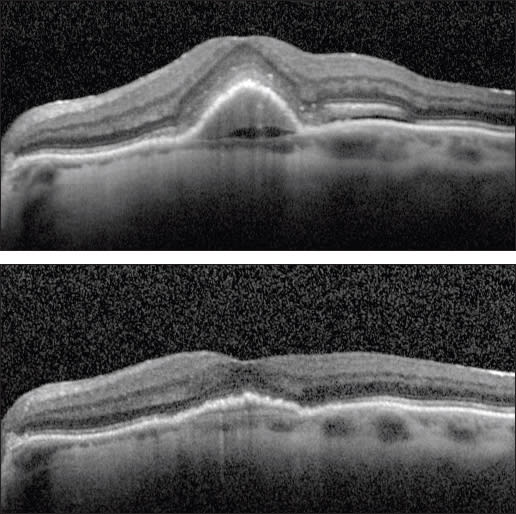

Case 2. The second case involved a 99-year-old woman who presented with a new occult lesion in the left eye. There was loss of one line of vision at 20/40, and a new PED with associated subretinal fluid was noted on her OCT (Figure 2A). She was treated with three doses of monthly bevacizumab with a minimal response, and her vision declined to 20/50+2 (Figure 2B).

She was then switched to monthly ranibizumab. The subretinal fluid resolved with one injection, and her vision improved to 20/30. However, after nine injections of monthly ranibizumab, her vision declined to 20/40, with a small amount of intraretinal fluid and an enlarging PED (Figure 2C). This visit coincided with the commercially availability of aflibercept, and the treatment was changed to monthly 2.0 mg aflibercept. After two injections, her vision improved to 20/30, the PED flattened, and the subretinal fluid resolved (Figure 2D).

Figure 2. A new occult CNV with PED (A). After treatment with bevacizumab, OCT showed persistent subretinal fluid (B). The therapy was switched to ranibizumab, and after nine injections, the PED had slightly grown in size, but the subretinal fluid had resolved (C). Due to PED growth, the patient was switched to aflibercept, and after two injections, the subretinal fluid resolved, and the PED flattened (D).